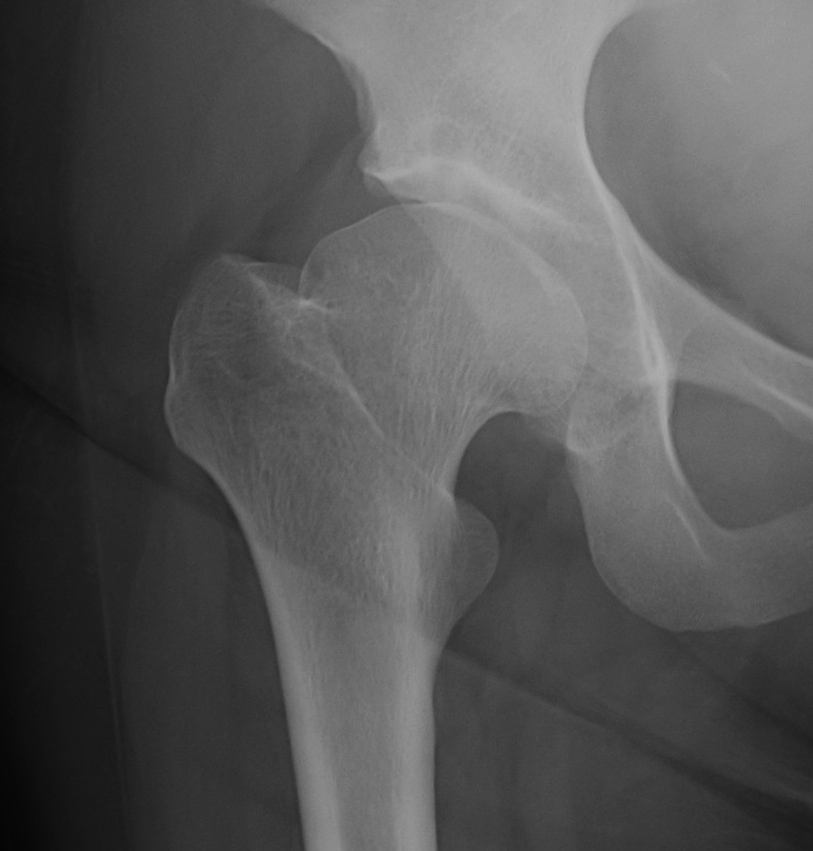

Etiology

Primary OA: 50%

Secondary OA: 50%